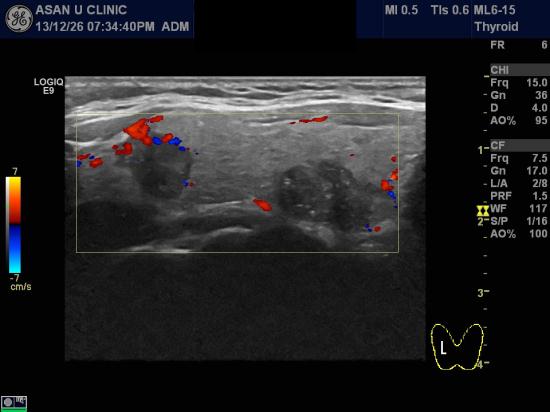

아산유외과 개원 후 16번째 갑상선암 진단.

유방암으로 수술받은후 경과관찰위해 시행한 PET scan

이상소견 있어 의뢰된 48세 여성분입니다.

우측 갑상선에 1.5cm, 1.1cm 의 두개의 미세석회화를 포함한 혹이 있었으며

세침검사를 실시하여 두혹 모두 갑상선의 유두암으로 진단되었습니다.

유방암이 갑상선에 전이된 것이 아니라

별개로 갑상선암이 진단된 경우입니다.

유두암은 예후가 좋기에 치료후 유방암보다 경과가 훨씬 좋습니다.

빠른쾌유를 기도합니다.